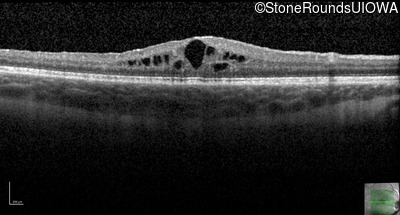

Age at visit: 7 years

OD OS

Age at visit: 9 years

Age at visit: 11 years